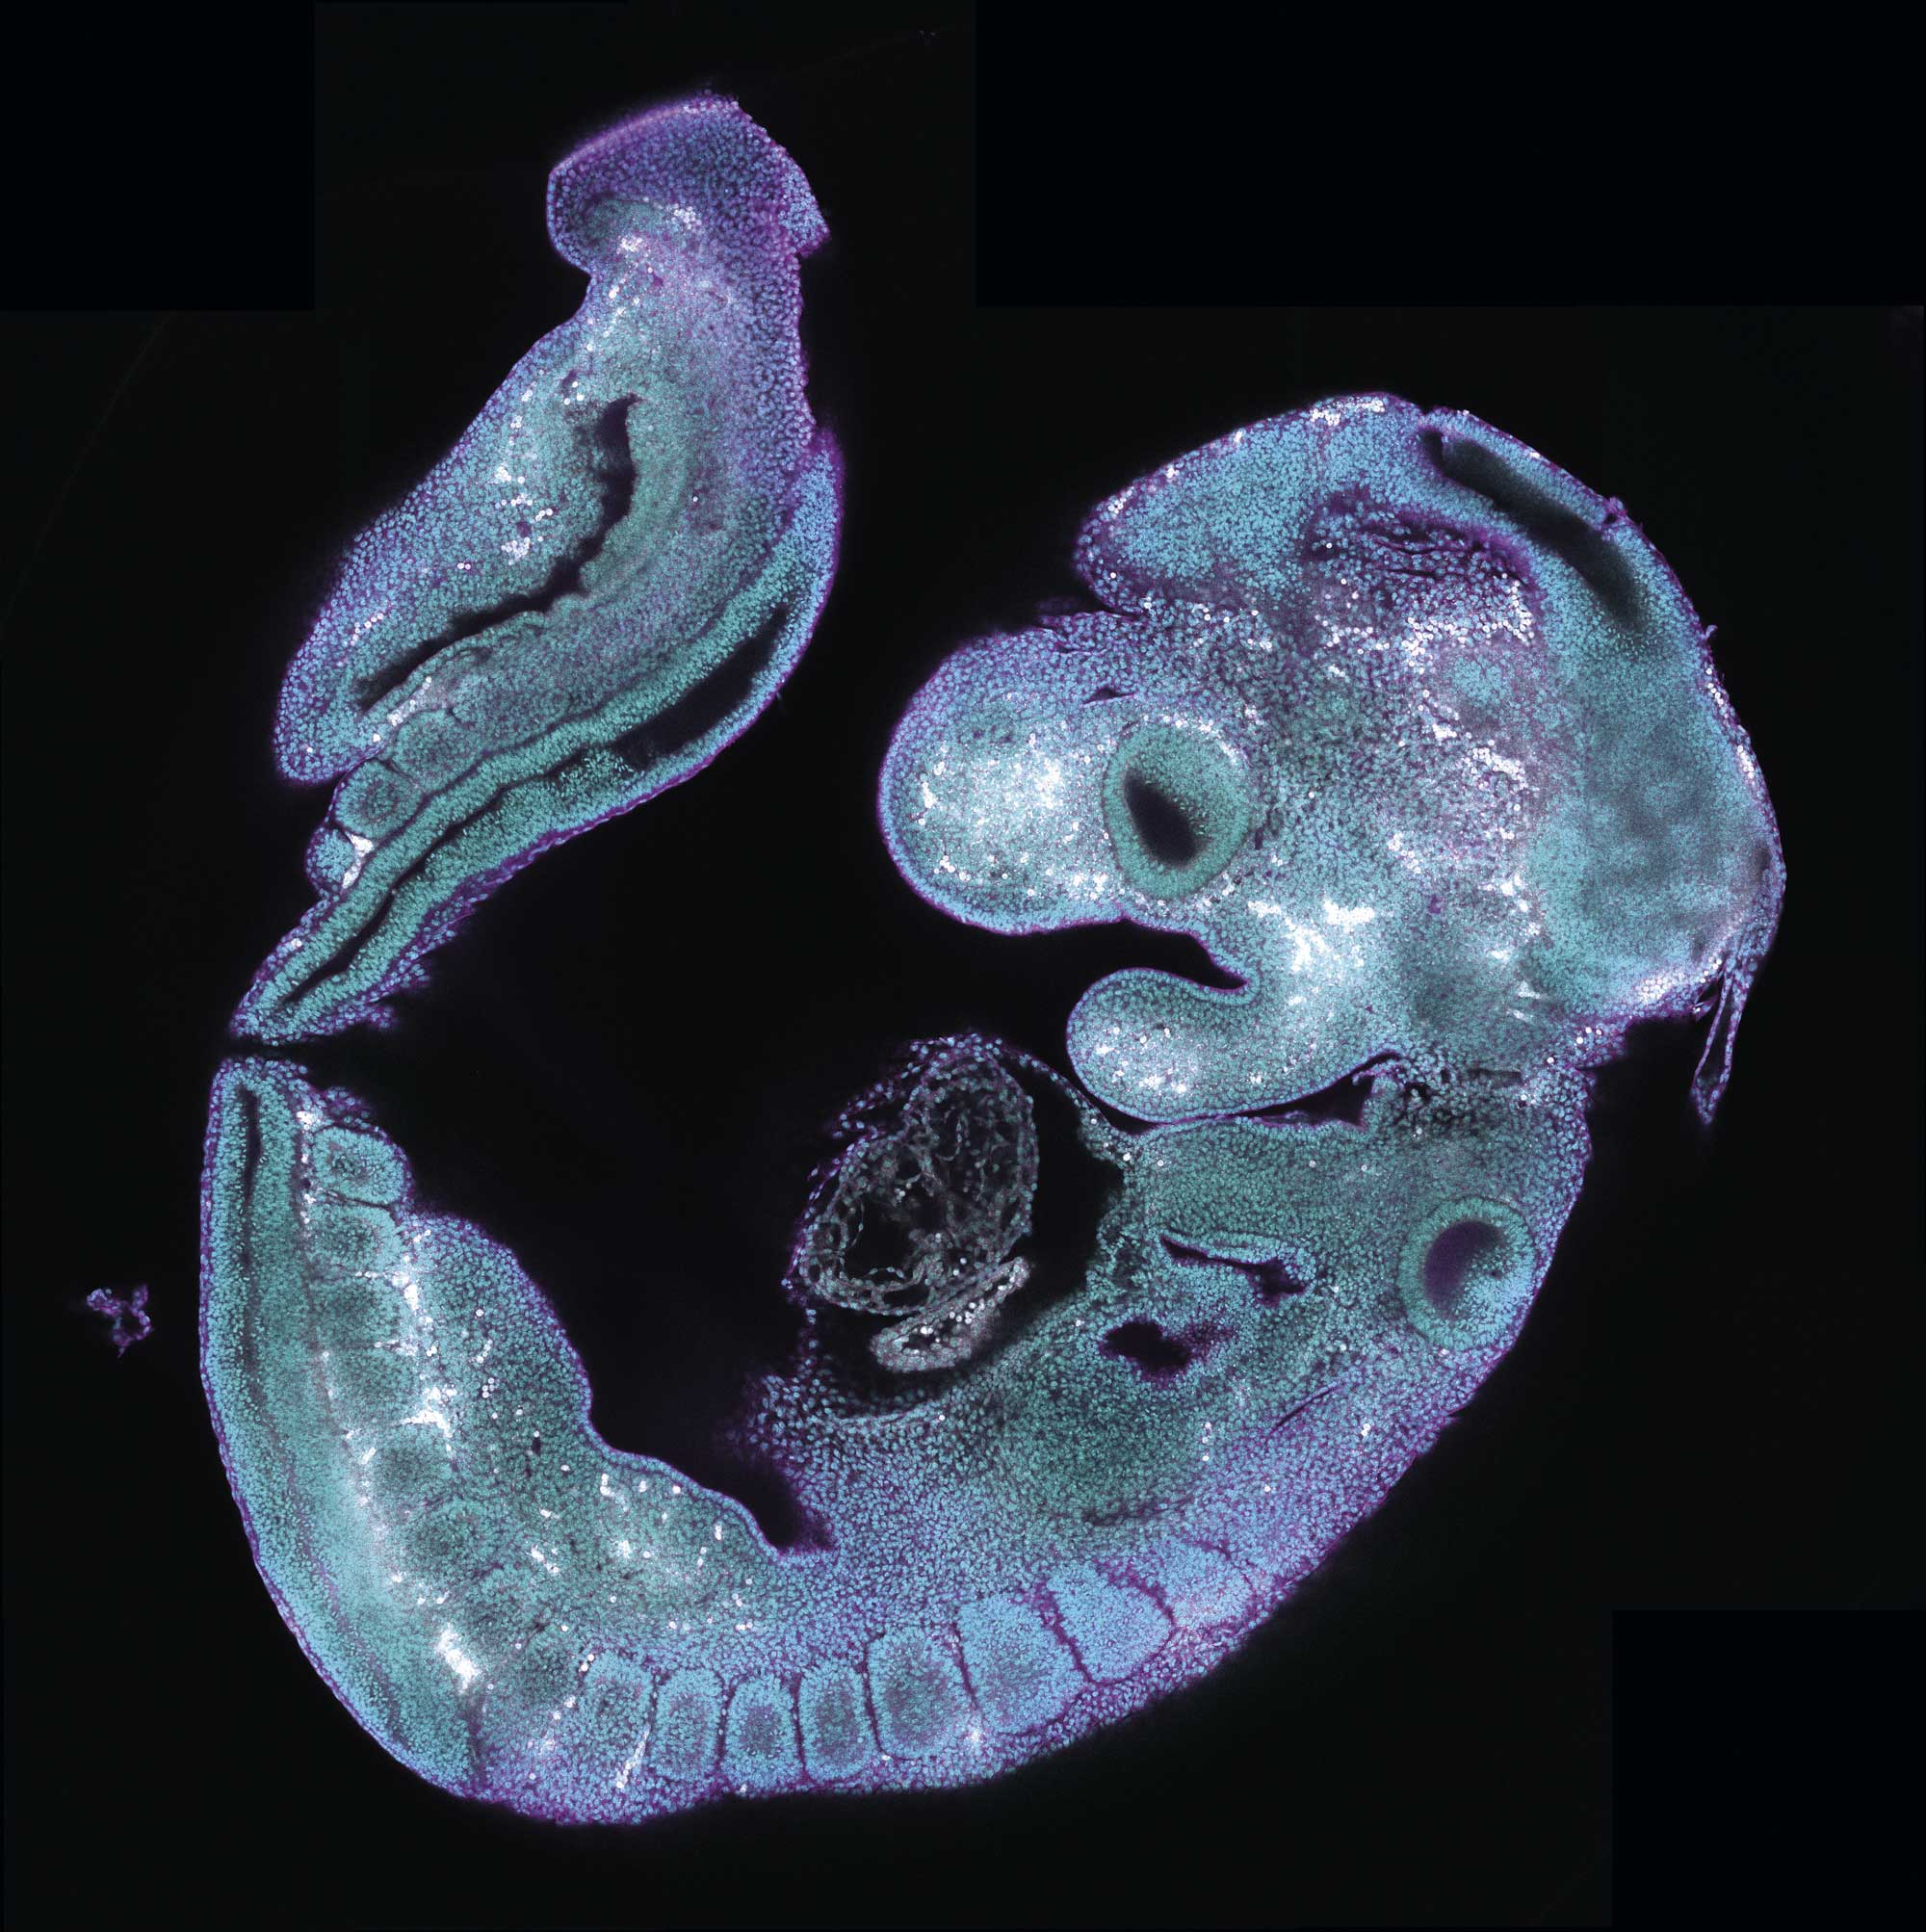

Electron microscopy studies revealed that mitochondria in Triadin-knockout myocytes are smaller and more abundant compared with wild-type cells, suggesting increased mitochondrial fission during disease progression (Figure 1).

Confocal microscopy confirmed that the mitochondria of Triadin-knockout cells have a heightened tendency to accumulate Ca2+, supporting the hypothesis that Ca2+ overload contributes to mitochondrial fission in Triadinknockout syndrome.

Ongoing research is investigating the molecular factors driving mitochondrial Ca2+ overload in Triadin-knockout cells and how this mishandling contributes to diastolic arrhythmogenesis.